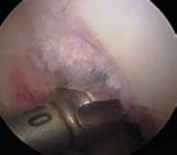

TECHNIQUES TECH FIG 1 • The posteromedial portal is established under direct visualization using a spinal needle. 1. Using an arthroscopic electrocautery device and shaver, overlying synovium and ruptured PCL fibers are débrided, and the superior interval between the ACL and PCL is defined.

2. An accessory posteromedial portal is created just proximal to the joint line and posterior to the MCL.

1. A 70-degree arthroscope is placed between the PCL remnants and the medial femoral condyle to assess the posterior horn of the medial meniscus and to localize the posteromedial portal with a spinal needle (

TECH FIG 1

).

2. A switching stick can be placed into the posteromedial portal to facilitate exchange of the arthroscope. The 30-degree arthroscope is used when viewing via the posteromedial portal.

5. If the AL bundle is found to be intact, special care is taken to preserve this bundle while the overlying synovium and ruptured PCL fibers are débrided (

TECH FIG 5A

26. Fixation and closure are then performed. TECH FIG 5 • A. An intact AL bundle is preserved and the overlying synovium and ruptured PCL fibers are débrided. B. The exit point for the tibial tunnel along the sloped face of the posterior tibial fossa is just distal and lateral to the intact PCL insertion, as demonstrated by a long 18-gauge bent wire

A B loop.